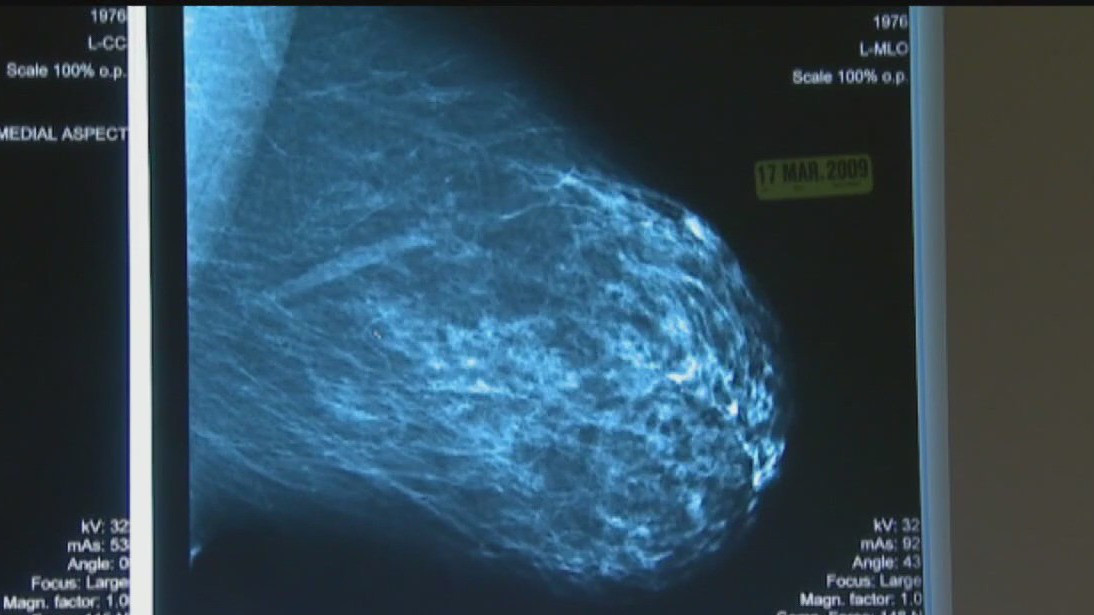

October marks National Breast Cancer Awareness Month

October is National Breast Cancer Awareness Month, marking a reminder for women to get their annual mammograms.